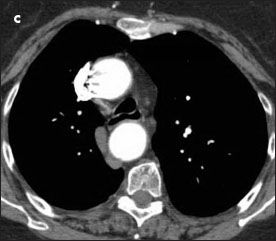

A high-resolution CT scan of the chest confirmed a right-sided aortic arch; a small ductus diverticulum was also noted just distal to the origin of the left subclavian artery, which was causing near circumferential compression of the trachea (Figure 2). Tracheal diameter at the thoracic inlet measured 1.1 cm, whereas maximal tracheal width at the level of greatest narrowing was 4 mm. Tracheal stenosis was strongly suspected.

Figure 2 – A highresolution CT scan of the chest confirmed the finding of a right-sided aortic arch and revealed marked narrowing of the trachea (B, yellow arrow) and a fibrous band between the left subclavian artery and the descending aorta (B, white arrow). The tracheal narrowing was apparent when comparing the view at the level of stenosis (B) with the cephalad (A) and caudad (C) views.